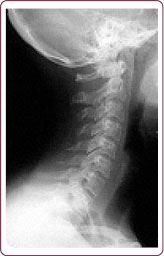

Нормальной статикой шеи считается небольшой физиологический лордоз (прогиб шеи вглубь) (рис. 3).

Рис. 3. Физиологический изгиб шейного отдела позвоночника